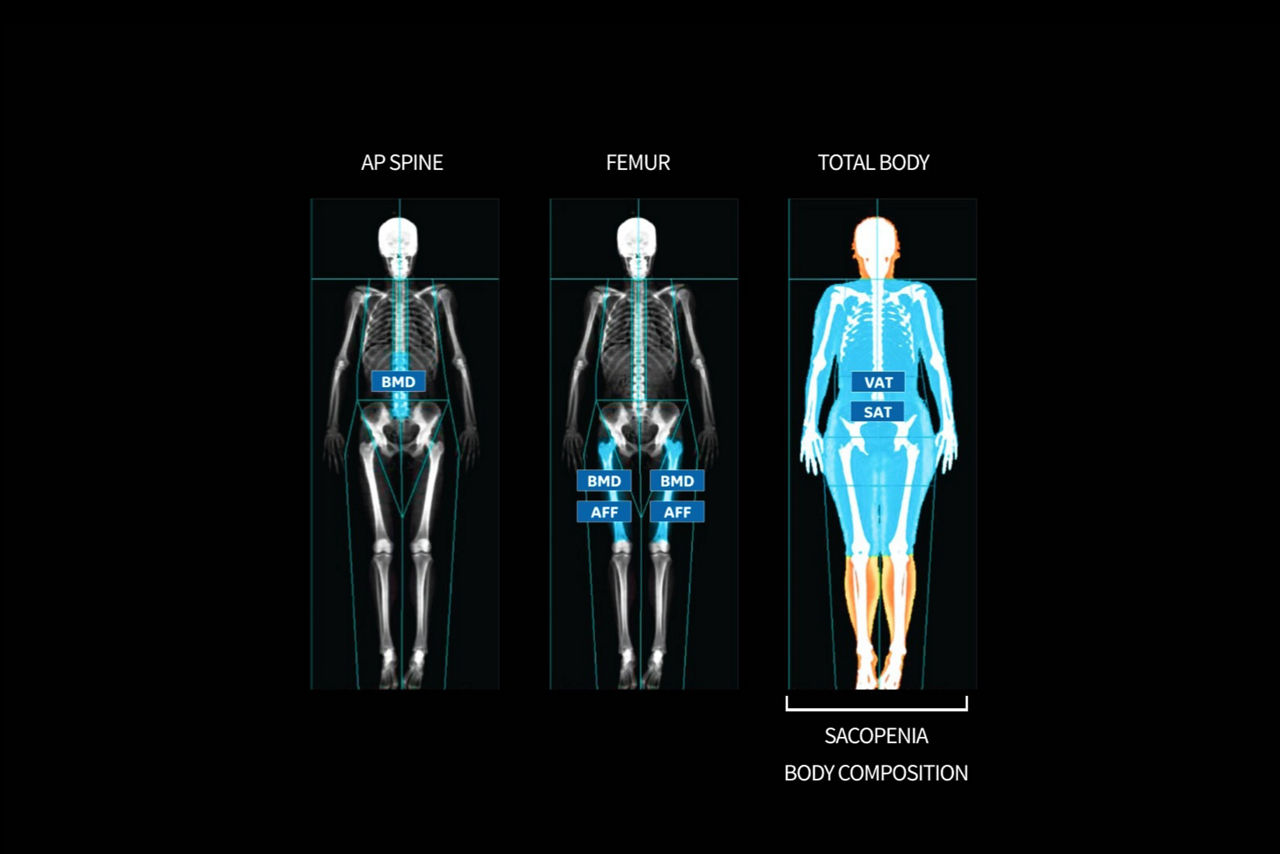

3. Jone W, Pearson A, Hind K, et al. 2022 Precision of the GE Lunar Total Body-LessHead Scan for the Measurement of Three-Compartment Body Composition inAthletes. J Clin Densitom 25(4): 692-698

4. Corescan for VAT and SAT, Sarcopenia, and AFF are all optional features thatmust be purchased for results to appear within DXAVision reporting